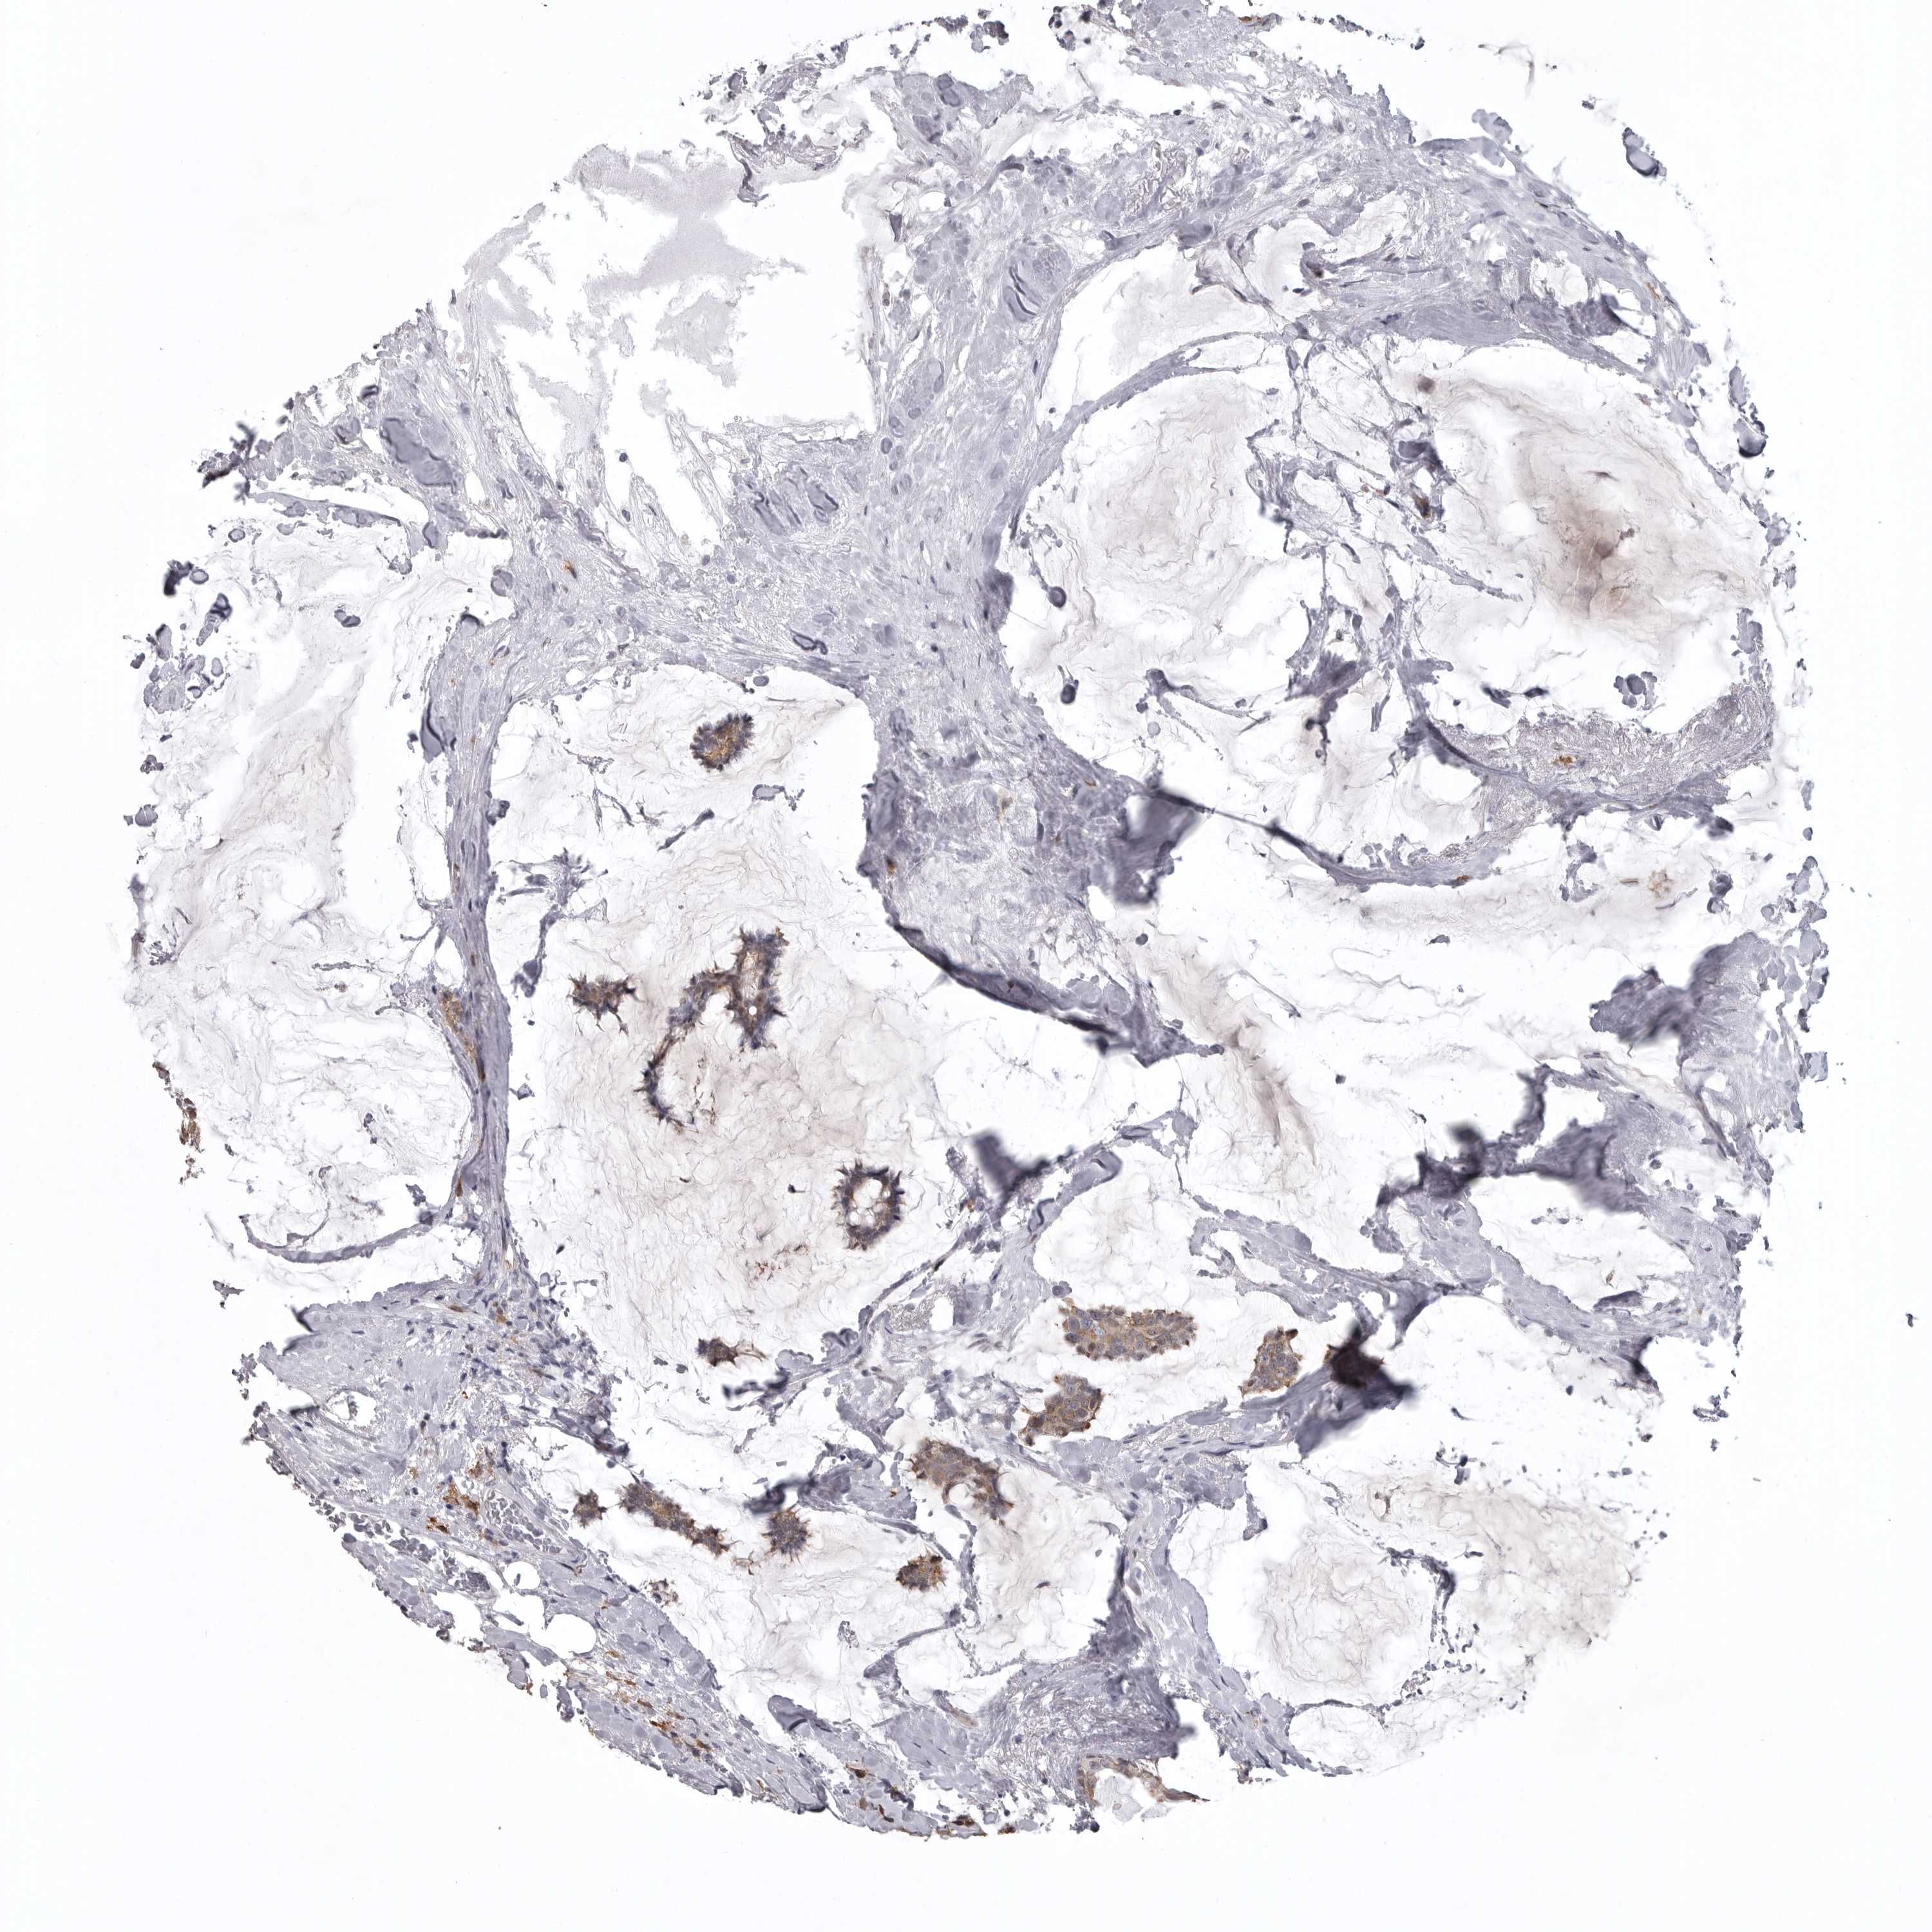

CANCER BREAST CANCER Show tissue menu

BRCA TCGA BRCA VALIDATION PROTEIN EXPRESSION